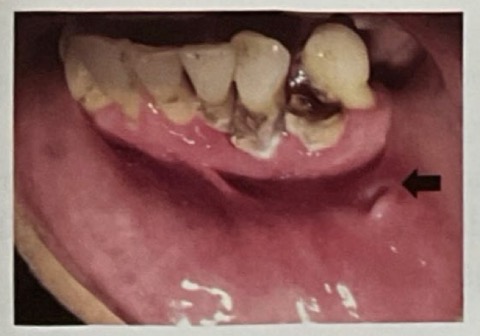

HOẠI TỬ XƯƠNG HÀM SAU XẠ TRỊ

CHẨN ĐOÁN ?